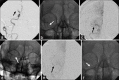

Solitaire FR device is a Food and Drug Administration-approved device for mechanical thrombectomy. It has been tested in various clinical trials for its safety and efficacy. We report a case of inadvertent detachment of the Solitaire FR device at stent-stent wire interface while performing mechanical thrombectomy. We review a rare phenomenon of retained Solitaire FR stent retriever in situ and discuss technique of avoidance and its management.